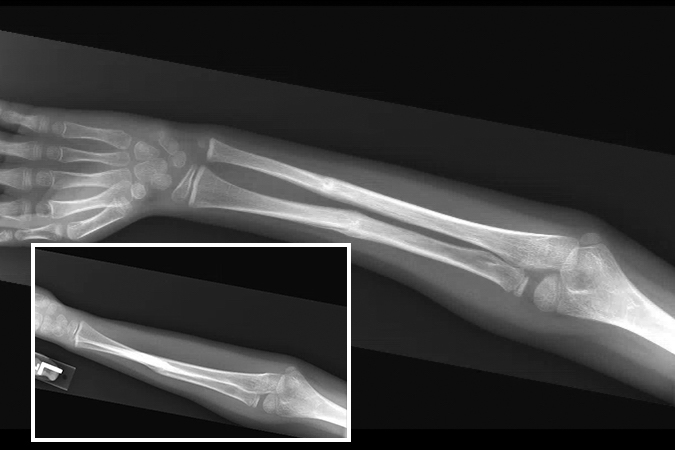

- A Monteggia fracture involves a fracture of the proximal third of the ulna combined with a subluxation or dislocation of the radial head at the proximal radioulnar joint (PRUJ) and the humeroradial joint.1,11,12

- These injuries most commonly occur secondary to a direct blow to the posterior aspect of the ulna, with the elbow extended and the forearm in hyperpronation.16,17

- Monteggia fractures account for <2% of all forearm fractures and are more common in pediatric patients than adults. In children and adolescents, they are usually caused by sports injuries, falls from a height, or motor vehicle accidents.11,13,16

Imaging17

- Radiology studies - X-ray

- AP and lateral orthogonal views with an oblique view are usually adequate.3